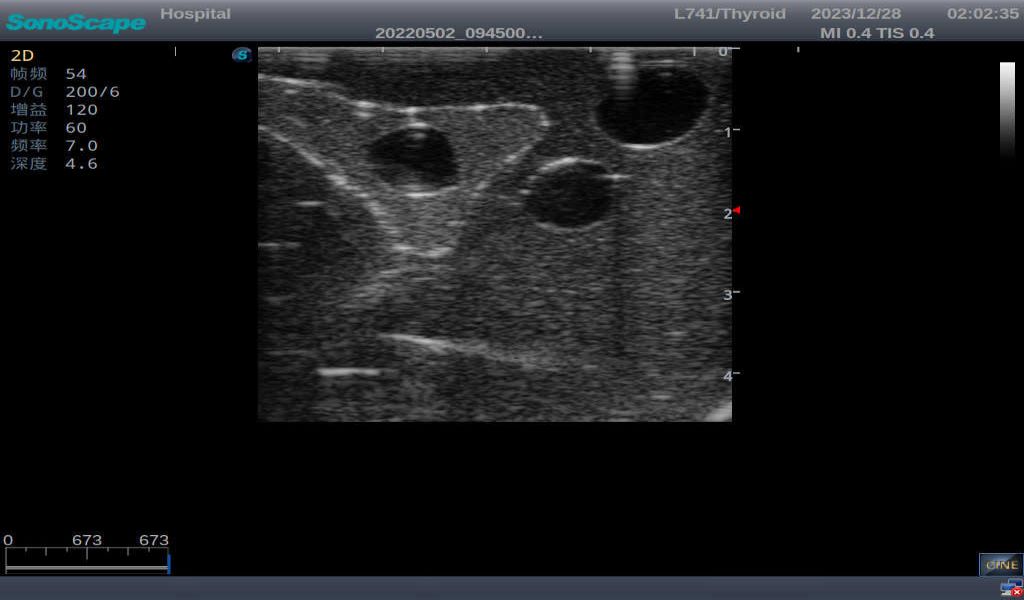

1)       Multi-position placement and fixation, helping different angles trainings

2)       Ultrasonically realistic materials at neck & various types of real ultrasonic machines in clinical available, developing realistic imaging like common carotid artery, internal jugular vein, trachea, thyroid cartilage, cricoid cartilage, lobes of thyroid gland and isthmus

3)       It comes with four (4) thyroid modules and can show five (5) ultrasonic images: normal thyroid, thyroid adenoma, thyroid cancer, nodular goiter, thyroid cyst

Thyroid cyst, which fluid area, dark and echo-free area can be seen